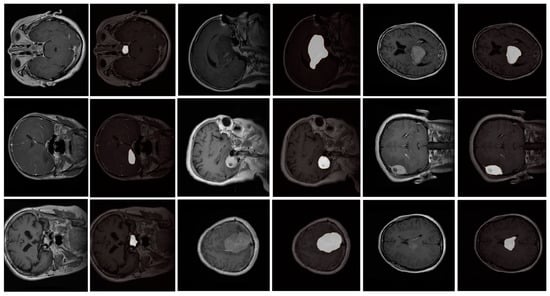

- Our model was evaluated on the Figshare dataset, which includes annotated MRI images of different brain tumor types: meningioma, glioma, and pituitary tumors. We provide a comprehensive comparison against leading segmentation models. Our results demonstrate that the proposed model achieves superior performance across metrics like accuracy, DSC, precision, and recall, confirming its robustness and reliability for clinical application.

4.1. The Dataset